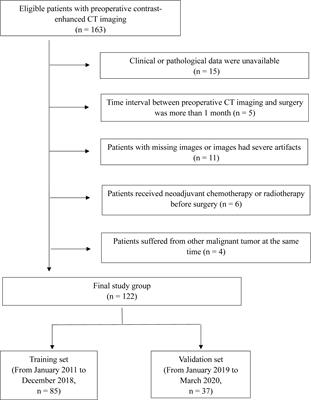

ORIGINAL RESEARCH

Published on 29 Jul 2021